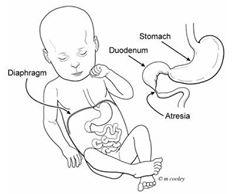

Duodenal atresia

What is duodenal atresia usually associated with?

Downs syndrome

What is the sonographic appearance of duodenal atresia?

Double bubble

polyhydramnios

Duodenal atresia

Double bubble

When can duodenal atresia be seen?

What causes a double bubble?

duodenal atresia

duodenal stenosis

annular pancreas

jejunal atresia